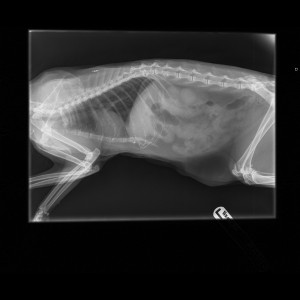

On Friday 13th, she was minding her own business at the end of her drive when a passing dog grabbed her on a long loose lead. The dog shook her, shattering her humerus (a bone in the upper forelimb). She managed to get free and scampered under the car for safety. The dog's owner allegedly made a sharp exit when a vigilant neighbour intercepted them. Once the owner knew what was occurring, Tilly got treated promptly at her vet's and Tilly was sent to us at West Midlands Veterinary Referrals for assessment and possible fracture fixation.

….This was an old cat with a horrendous fracture. Several fragments, splits, and fissures extended to the top of the bone. This fracture promised to be extremely tricky to fix. Fixation failure was possible, and Tilly would need to be cage confined for several weeks. She doesn’t do much except potter up and down the drive, so we felt that amputation was the best option for this cat. Amputation is quick, predictable in the outcome and involves little in the way of aftercare.